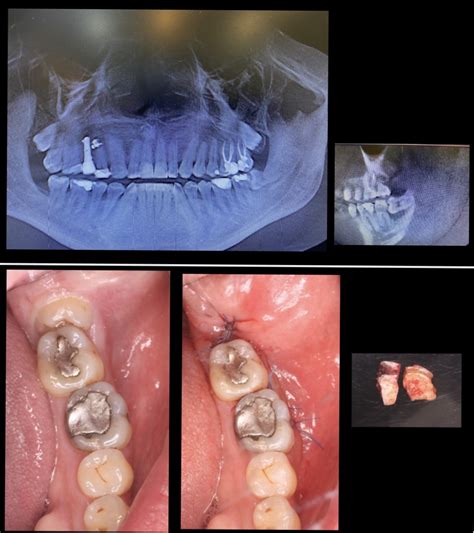

Por lo general, las caries superficiales, que afectan al esmalte y que no han sido tratadas con una obturación o empaste, pueden seguir avanzando hacia el interior del diente, dañando la pulpa dentaria. Cuando, efectivamente, la pieza dental está infectada, antes de realizar cualquier tratamiento, es necesario que el paciente tome antibióticos para eliminarla. De esta manera, posteriormente, podremos tratar el motivo que la ha originado.

En muchos casos, podemos realizar una endodoncia, con la que podemos salvar la pieza. De esta manera, por lo tanto, un diente o una muela con una infección activa no puede extraerse ni recibir ningún tipo de tratamiento odontológico conservador. Sin embargo, existen algunas excepciones, en las que se puede actuar al momento, siempre bajo el criterio del facultativo. Por ejemplo, ante un absceso localizado de pus, se puede drenar para ayudar a la acción del medicamente.

Igualmente, se pueden realizar aperturas camerales en un diente para drenar la supuración y, posteriormente, llevar a cabo el tratamiento de conductos con la infección controlada. Si sientes dolor en un diente o una muela, no dejes pasar el tiempo y visita a tu dentista.

Los tratamientos para una muela infectada pueden incluir un empaste dental, una endodoncia, o la extracción de la muela completa o sus restos radiculares.

- Empaste dental: Cuando la causa que ha originado la infección es una caries, uno de los tratamientos más habituales es el empaste dental. El objetivo final del empaste, además de retirar la caries, es realizar un buen sellado de la muela para evitar la posterior entrada de bacterias.

- Endodoncia: Mediante una endodoncia, el dentista accederá hasta la pulpa y la limpiará completamente. La endodoncia es conocida coloquialmente con la expresión “matar el nervio”. Esto se debe a que el nervio dental se elimina y se sustituye por el material que acabamos de mencionar.

- Extracción de la pieza dental: Hay casos en los que la muela no puede salvarse mediante un empaste o una endodoncia ya que sufre una destrucción muy severa de su estructura y no puede reconstruirse con garantías. En este caso, lo más probable es que se tenga que extraer la pieza dental completa. Antes de comenzar con la extracción, el dentista aplicará anestesia local para que el paciente no experimente dolor ni molestias durante la intervención. Una vez haya anestesiado, el odontólogo utilizará su instrumental para separar el diente de la encía y extraerlo. Tras la extracción, el profesional limpiará el hueco que ha dejado la muela y eliminará todos los restos de infección que hayan quedado en la cavidad.